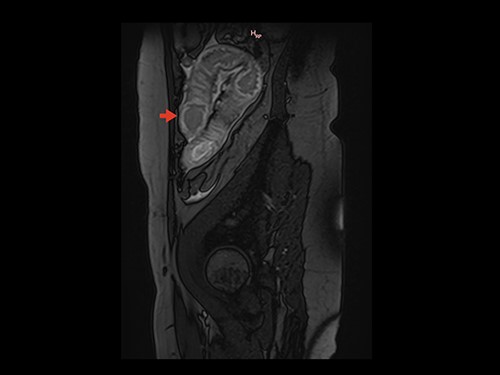

Magnetic resonance image (MRI) was performed. MVT and venous ischemia of a small bowel loop were identified (Figs 1 and 2). She underwent a diagnostic laparoscopy that showed hemorrhagic content in the pelvis and omental plastron surrounding an ischemic bowel loop. The procedure was converted and enterectomy was performed (Fig. 3).

Sagittal section on MRI showing parietal thickening of the intestinal wall. Arrow: thickened intestinal wall.